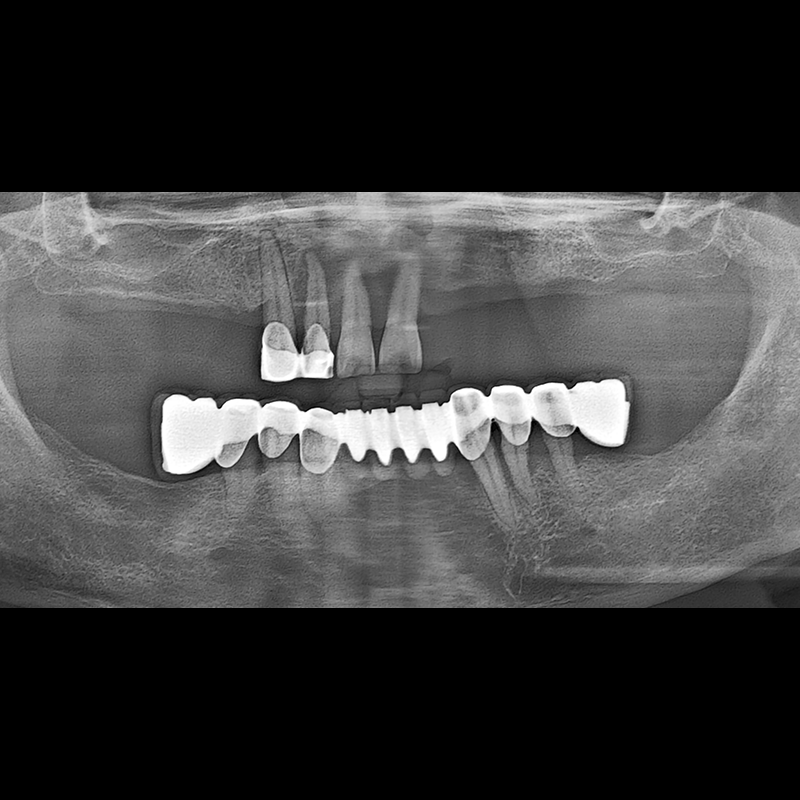

BEFORE AFTER

Implant before and after 2025.05.30

Implants were placed in the missing tooth and in the tooth position where it was difficult to save.